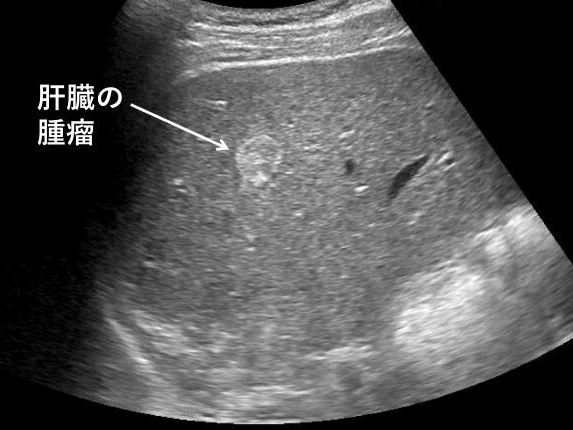

- 간암

Q3. 복부 초음파만으로 암 진단이 가능한가요?

A3. 암의 초기 징후(덩이, 구조 변화 등)는 초음파로 확인할 수 있으나 확진을 위해서는 CT, MRI, 조직검사 등이 추가로 필요할 수 있습니다.